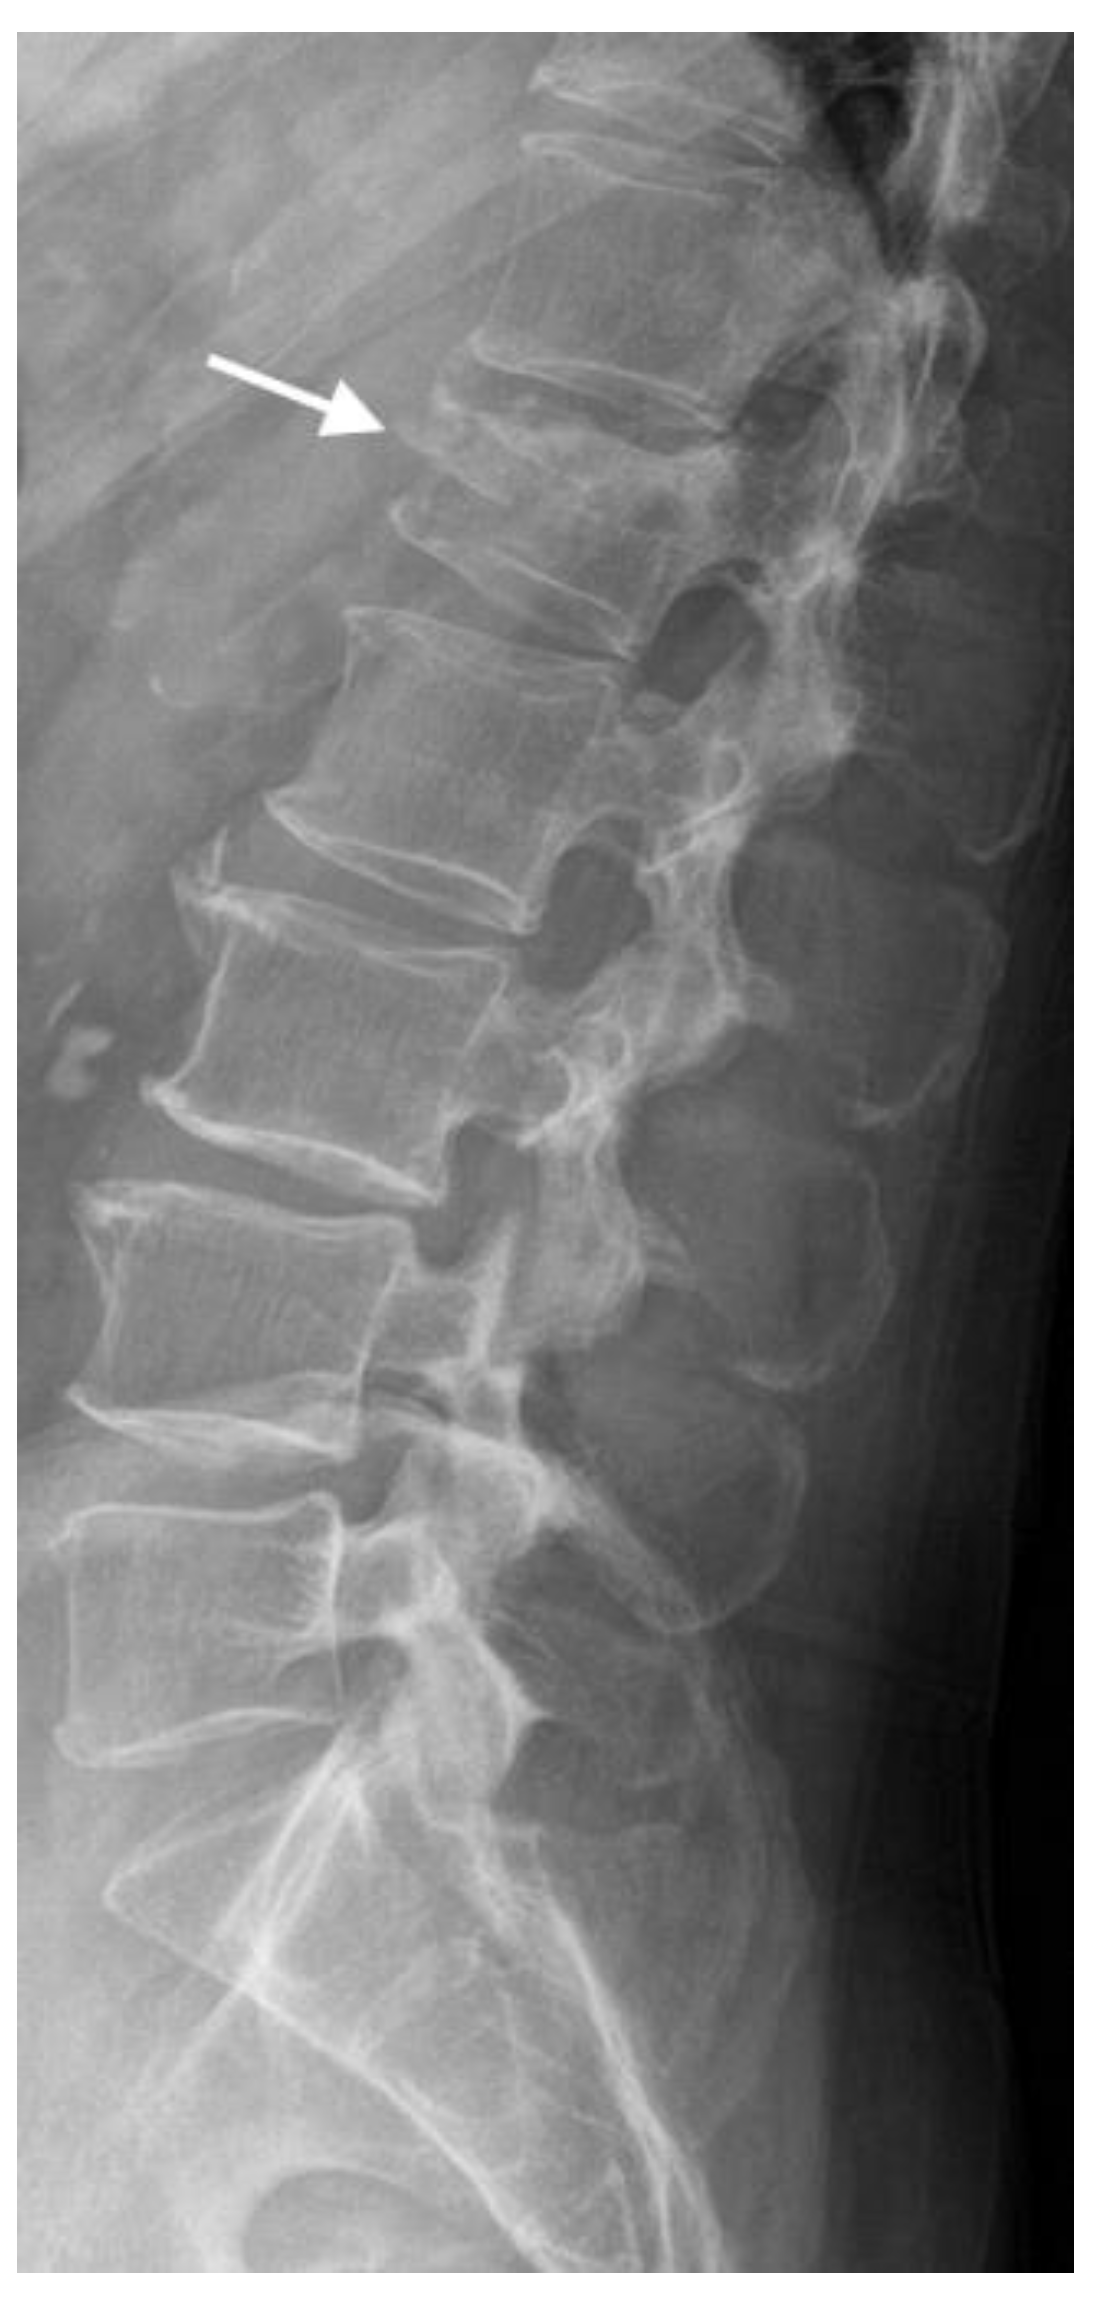

4.1. Radiographs